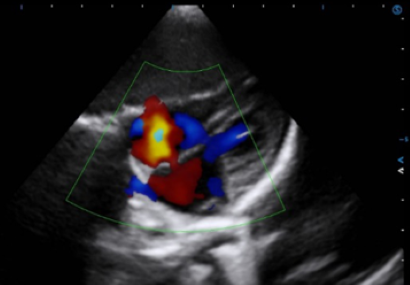

Auto EF facilitates cardiac systolic function assessment by automatically identifying and tracking the endocardium, and accurately calculating the LV EF within seconds.

Auto SG empowers objective evaluation of LV systolic function and myocardial deformation through quantitative results in a bull’s-eye plot.

TDI QA quantitatively analyzes the myocardial motion with multiple sampling points for convenient comparison and evaluation.

Stress Echo analyzes myocardial motion at rest and under stress to help evaluate how coronary arteries respond to the stress.